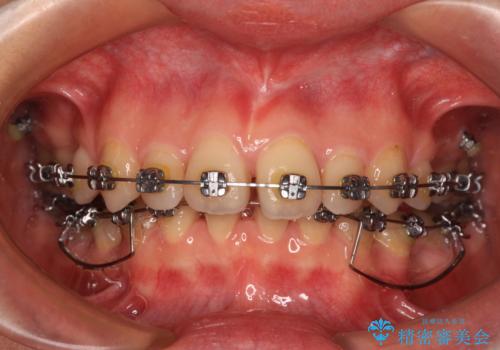

- メタルブラケット

乳歯を残し、欠損部位のスペースを適正な幅に拡大し、インプラント補綴治療により歯列を整える治療も考えられましたが、ご本人から飛び出している前歯をどうしても引っ込めたいとの要望があったため、残存乳歯ならびに上顎左右第二小臼歯を抜歯して、歯列を整えることとしました。

上下臼歯の咬み合わせ改善には補助装置を、深い咬み合わせ改善にはユーティリティーアーチを活用し、ワイヤー装置にて矯正治療を行うこととしました。